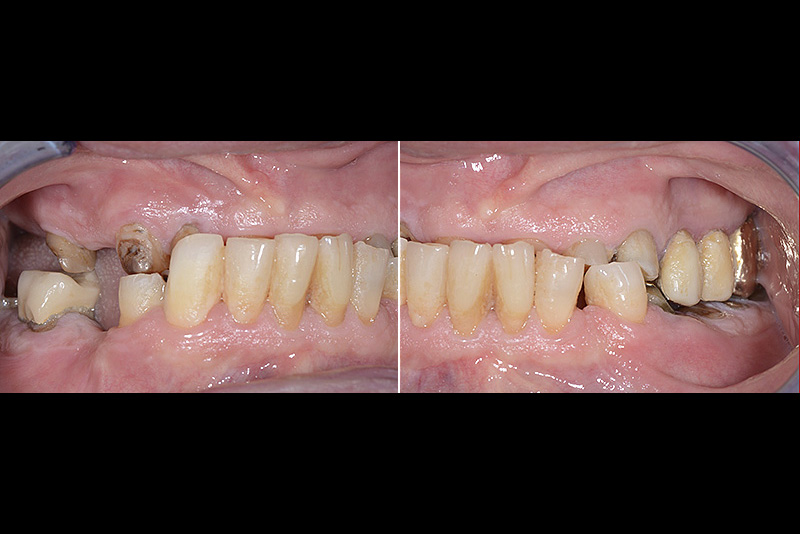

PREMESSA: in seguito all’estrazione dell’incisivo laterale superiore di destra, resasi necessaria per cause batteriche, si decide di affrontare il caso con il posizionamento di un impianto in sostituzione dell’elemento mancante dopo guarigione del sito infetto. Con tecniche rigenerative sia dei tessuti ossei mancanti a causa dell’infezione pregressa, sia dei tessuti gengivali che appaiono inizialmente troppo spostati in alto, si ripristina una corretta morfologia delle parabole (contorni) gengivali e delle papille interdentali (triangoli di gengiva tra due denti vicini).